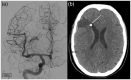

Ruptured arteriovenous malformations are a frequently encountered pathology with significant associated morbidity and mortality. Identifying and securing the rupture point is mandatory; however, this can often be difficult. Black blood vessel wall magnetic resonance imaging is a promising technique for identifying ruptured saccular aneurysms and has been used in cases of multiple aneurysms. Here we describe a case of using this imaging technique to identify the rupture point in a ruptured arteriovenous malformation with histopathological correlation.